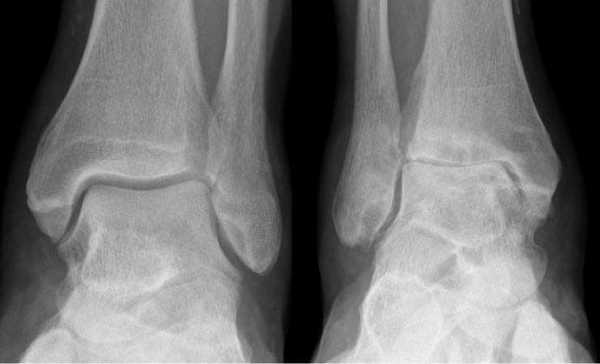

Не смотря на то, что Loomer с соавт. сообщили, что только от 50% до 66% остеохондральных дефектов обнаруживаются при помощи обычной рентгенографии, данный метод является важной отправной точкой и может быть полезен для исключения другой патологии голеностопного сустава [20]. Рентгенологическое исследование голеностопного сустава должно включать переднюю, заднюю и в 3⁄4 внутренней ротации проекции. Все проекции выполняются стоя (под нагрузкой) и называются функциональными. Функциональные рентгенограммы могут быть полезны для выявления сопутствующей нестабильности голеностопного сустава, проекция 3⁄4 во внутренней ротации, помогает в визуализации щели межберцового синдесмоза, а так же отображает передне-внутрений импижмент (таранной и большеберцовой кости) в случае его наличия. Выполненные в положении подошвенного сгибания прямая и 3⁄4 проекция во внутренней ротации могут быть полезны в выявлении заднемедиального поражения таранной кости. Рентгенологические признаки, которые могут быть определены, варьируются от небольших участков сдавления субхондральной кости до крупных отслоенных остеохондральных фрагментов. Радиографическая

система классификации была разработана Berndt и Harty в 1959 году и остается золотым стандартом. (Табл. 1) [16]. Loomer с соавторами дополнили имеющуюся классификацию, на основе не только рентгенограмм, а также МРТ (магнитно-резонансная томография) и КТ (компьютерная томография), и добавили стадию V в систему классификации Berndt и Harty [22].